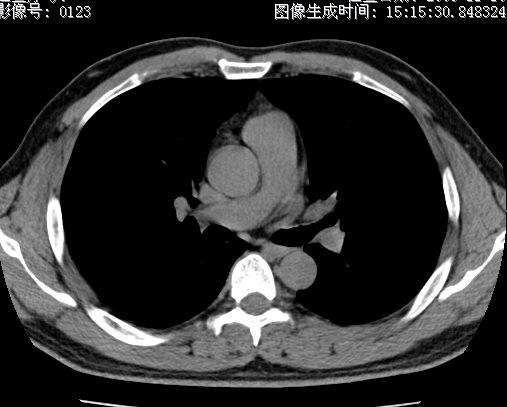

以下是引用zhao_bin2008在2010-1-4 20:15:00的发言:[br]先天性肺囊肿或小的肺隔离症?

以下是引用卜一在2010-1-4 22:09:00的发言:[br]先天性肺囊肿或小的肺隔离症?支持!

以下是引用zsl6918在2010-1-5 5:23:00的发言:[br]良性改变!肺囊肿,先天性支气管闭锁,血管畸形等均有可能。

以下是引用影像之路在2010-1-6 11:10:00的发言:[br]腺癌,最终的病检有些出乎意料之外,术前同志们大多考虑为肺囊肿或小的肺隔离征 [br]回过头来看 小结节呈分叶状,其内侧有一条较粗的静脉供血或许能成为支持诊断腺癌的理由